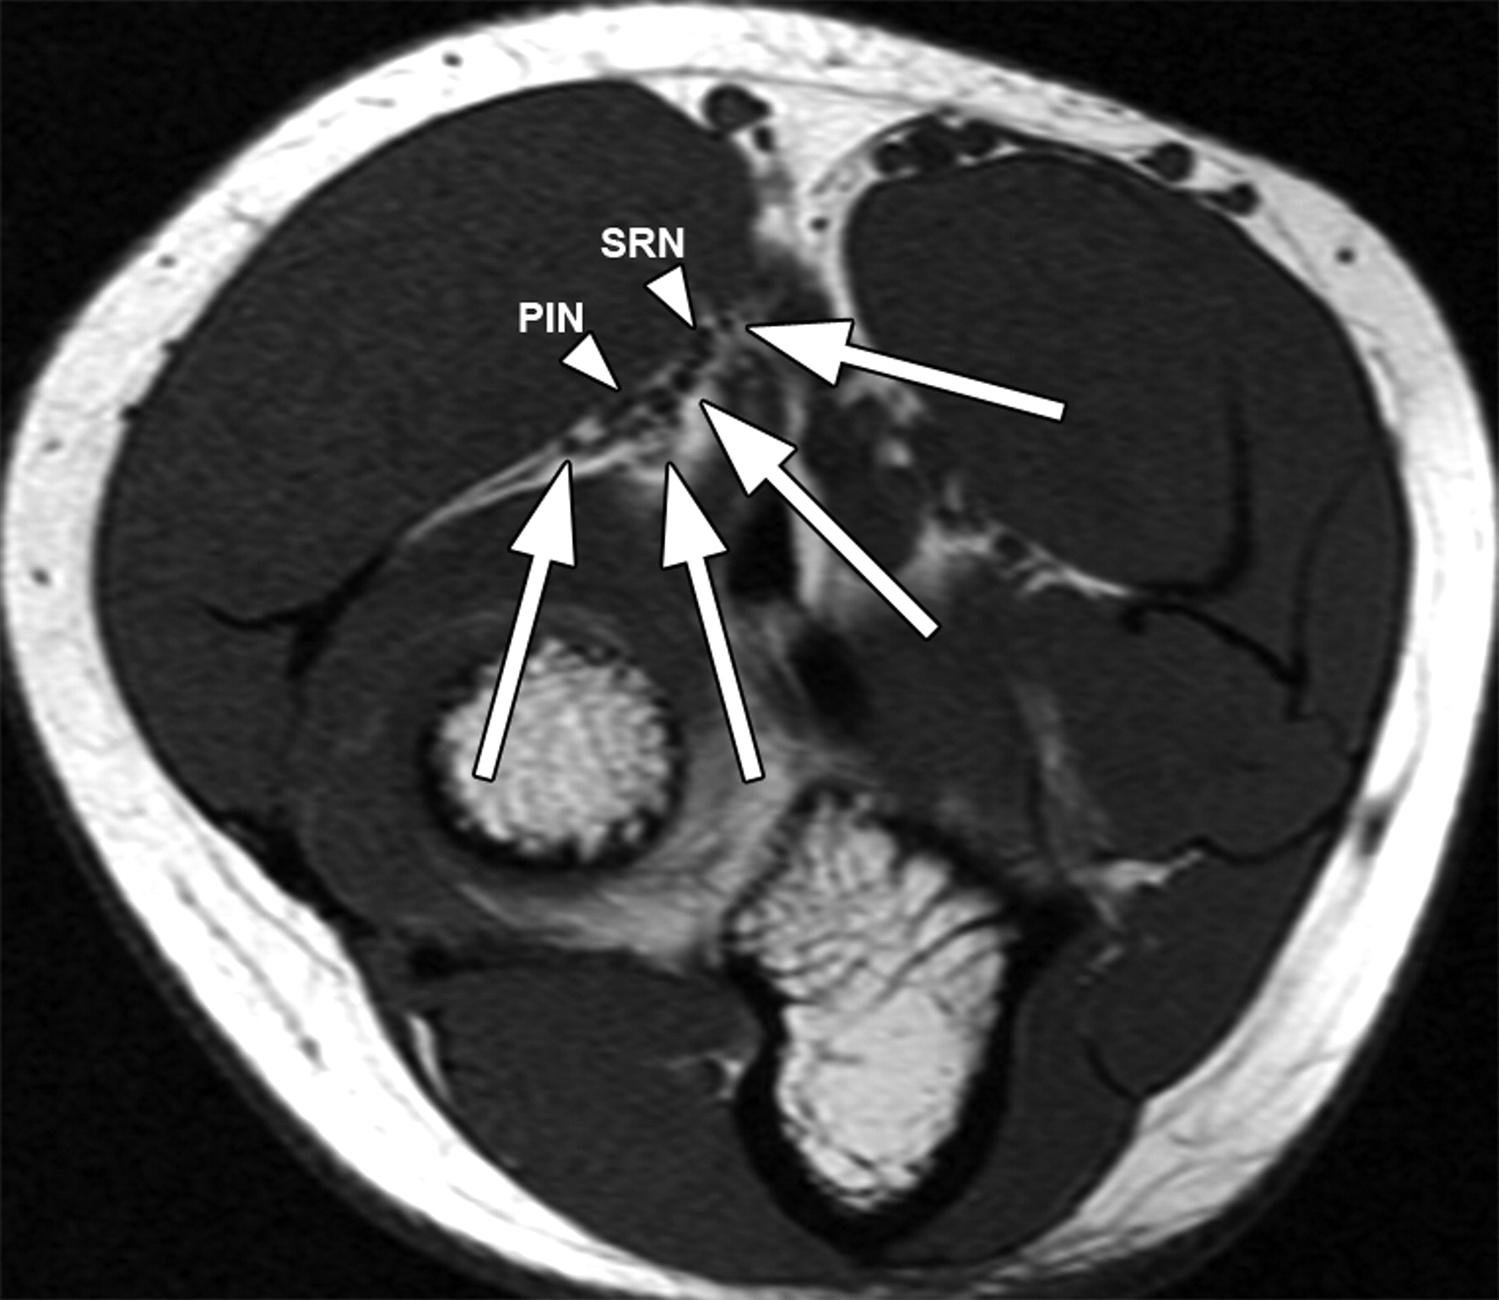

Axial T2WI with FS of a patient with a radial tunnel syndrome showing Can An Mri Detect Radial Tunnel Syndrome Electromyography (emg) and nerve conduction studies (ncs) are often normal in. Mri studies my show muscle edema or atrophy along the distribution of the posterior interosseous nerve. There are no clear tests to diagnose radial tunnel syndrome. Radial tunnel syndrome is a compressive neuropathy of the posterior interosseous nerve (pin) at the level of proximal forearm (radial tunnel). Diagnosis is. Can An Mri Detect Radial Tunnel Syndrome.